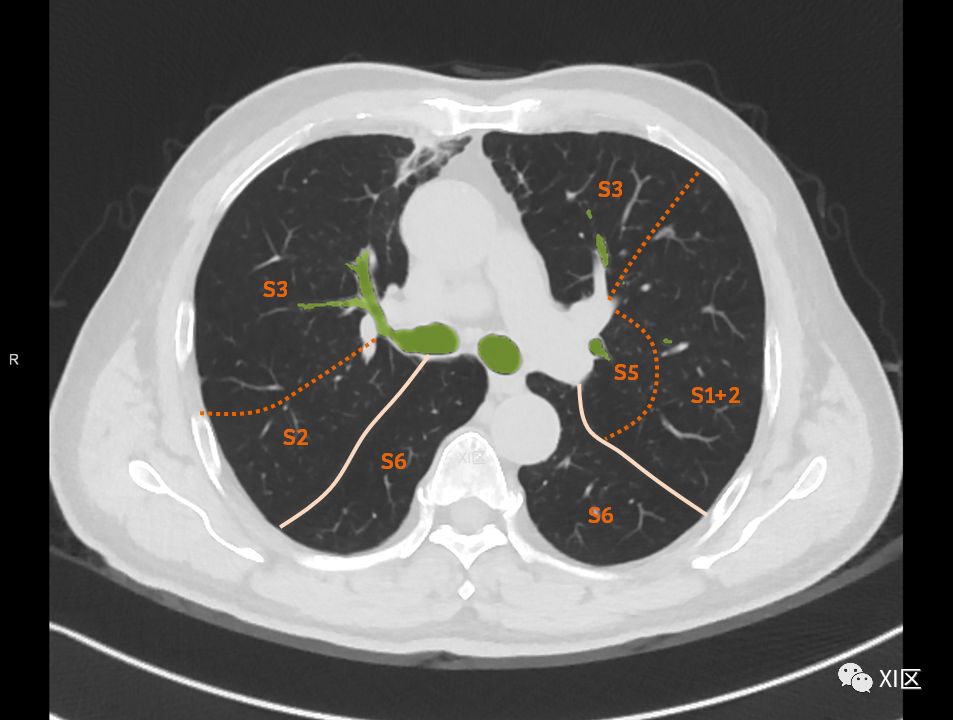

在进行肺的分段时,可以上下观察浏览,沿着相应气管的走形可以更容易准确地进行分段。

肺的分段

肺的断层分段示意图